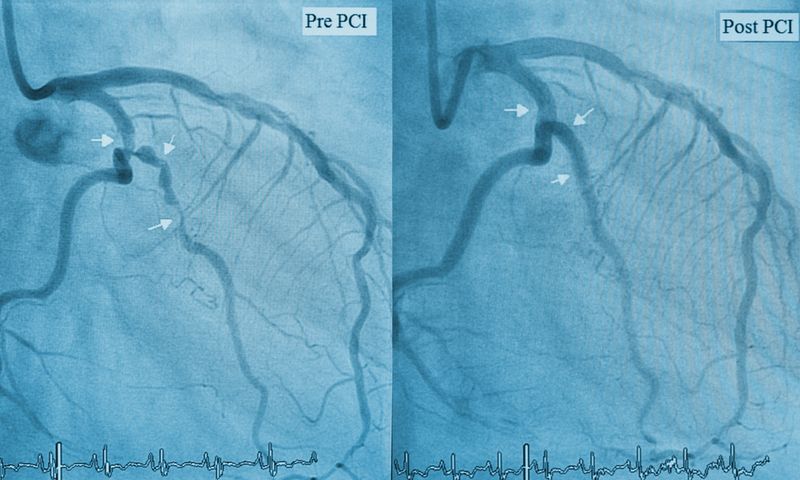

Ein behandlungsbedingter Herzinfarkt während der Stent-Behandlung wird neben offensichtlichen Beschwerden der Patientin beziehungsweise des Patienten sowie Veränderungen des EKGs durch Marker im Blut (Biomarker) nachgewiesen. Die heute verwendeten Biomarker (hsTNT) sind sehr sensibel und zeigen bereits minimalste Herzmuskelschäden an. Ab welchem Biomarker-Schwellenwert von einem behandlungsbedingten Herzinfarkt ausgegangen werden soll, ist unter Fachleuten umstritten. Weltweit sind drei Definitionen in Diskussion: Die «Universal Definition of MI» wurde von einer Taskforce der Europäischen und Amerikanischen Gesellschaft für Kardiologie entwickelt. Daneben existieren eine Definition des International Academic Research Consortium sowie eine der Amerikanischen Gesellschaft für Invasive Kardiologie. Die Universitätsklinik für Kardiologie am Inselspital misst ihre Behandlungsergebnisse nach Stent-Implantation seit 2009 routinemässig und verfügt so über einen Datensatz von über 20'000 Patientinnen und Patienten. Dadurch konnte sie eine trennscharfe Überprüfung der Auswirkungen der drei Definitionen vornehmen. Die seit längerer Zeit kontrovers geführte Debatte kann aufgrund dieser Resultaten voraussichtlich beendet werden.